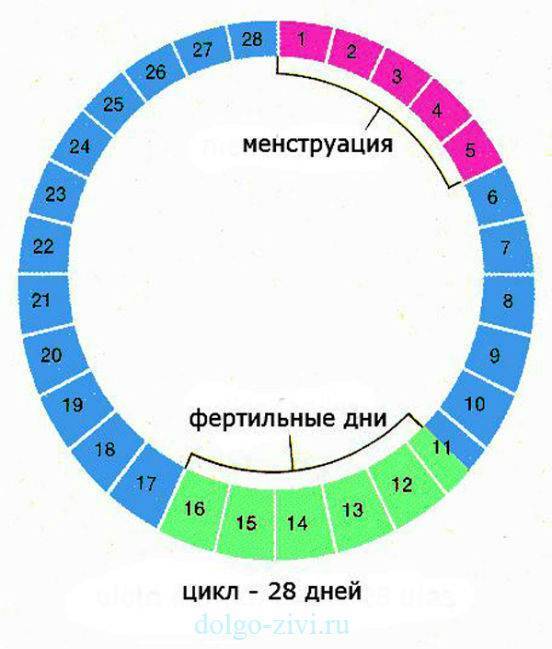

Рекомендации по зачатии